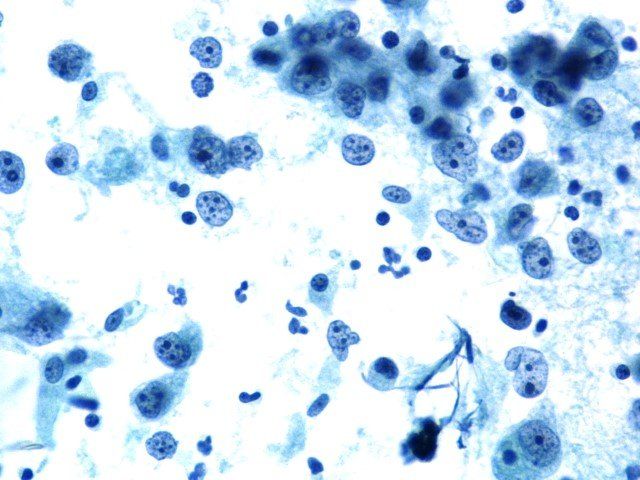

Fluid Romanowsky - Diagnostic Cytology Scheme.

This slide shows excellent staining of both nucleus and cytoplasm.

This scored 9/10 at assessment.